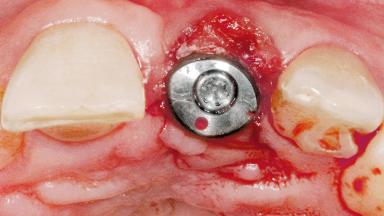

Late Flapless Placement of an Implant in a Maxillary Left Central Incisor Site

Type of Implants One-Piece

Bone Augmentation Horizontal|Staged

Augmentation Materials Xenogenous|Membrane

Soft Tissue Grafting Simultaneous